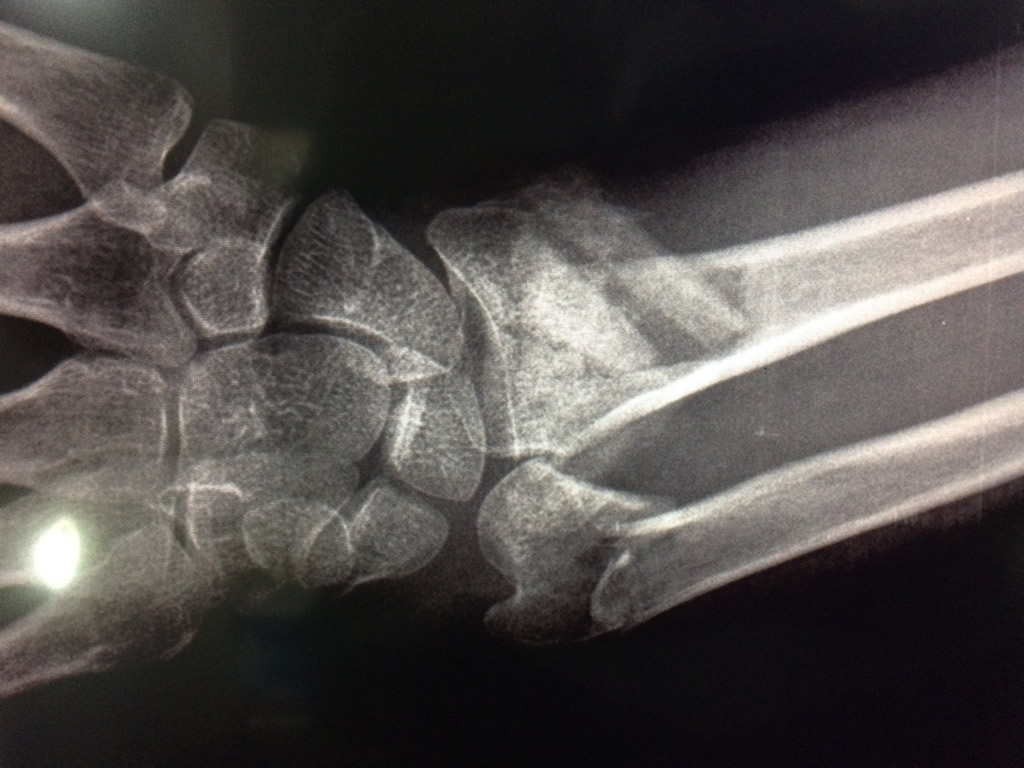

Los procedimientos más comunes en cirugía de la mano son aquellos destinados a reparar traumatismos, incluyendo lesiones de tendones, nervios, vasos sanguíneos, y articulaciones; huesos fracturados; y quemaduras, cortes, y otros daños de la piel.